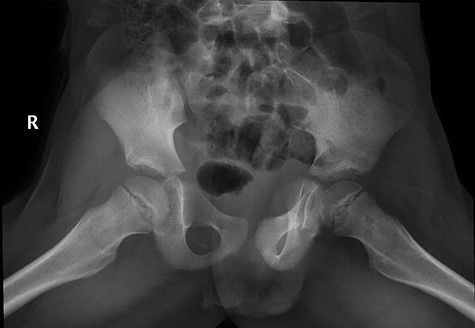

Patient was given adequate analgesia and routine blood tests were done (CRP 5.8 WBC 7.5x109). X-rays revealed small Lytic lesion with surrounding sclerosis at infero-medial aspect of left femoral neck in antero-posterior and lateral views (Fig. 1, 2).